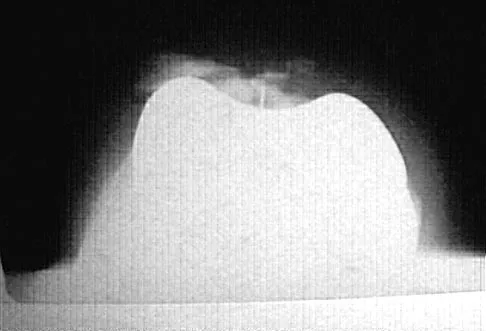

A 10-year-old boy has a painful, swollen knee after falling off his bicycle. Examination reveals that the knee is held in 45 degrees of flexion, and any attempt to actively or passively extend the knee produces pain and muscle spasms. A lateral radiograph is shown in Figure 4. What is the most likely diagnosis?

Explanation